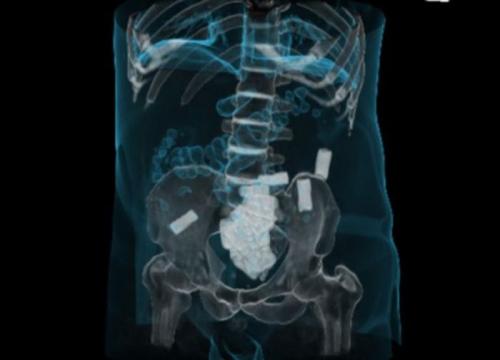

Рентгеновские снимки «лошадок» - людей, перевозящих небольшие партии наркотиков внутри своего тела. Если контейнеры с наркотиками раскрываются - человек умирает.

20 контейнеров с наркотиками в толстой кишке.